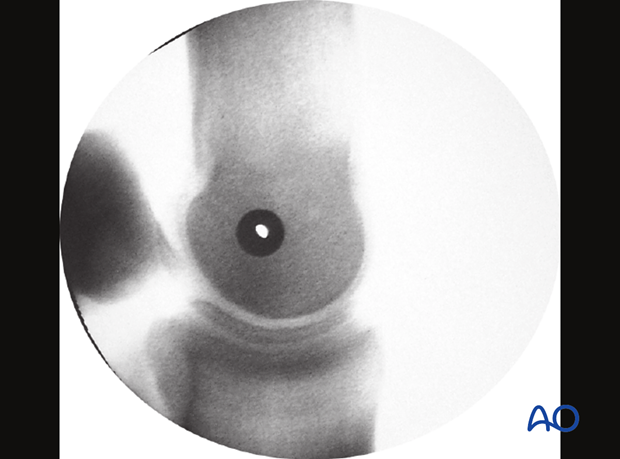

Ideally, one should check the positioning of the glide hole by taking a lateromedial radiographic view with the drill guide in place. If the hole in the drill guide is clearly visible and the proximal sesamoid bones are superimposed, the surgeon can be very confident that the screw will be properly directed across the condyle.

Ideally, a fluoroscopic view is taken to estimate if the screw length is correct. If correct, the screw is fully tightened. Some surgeons prefer to have the horse take weight off the limb while the final tightening is performed.